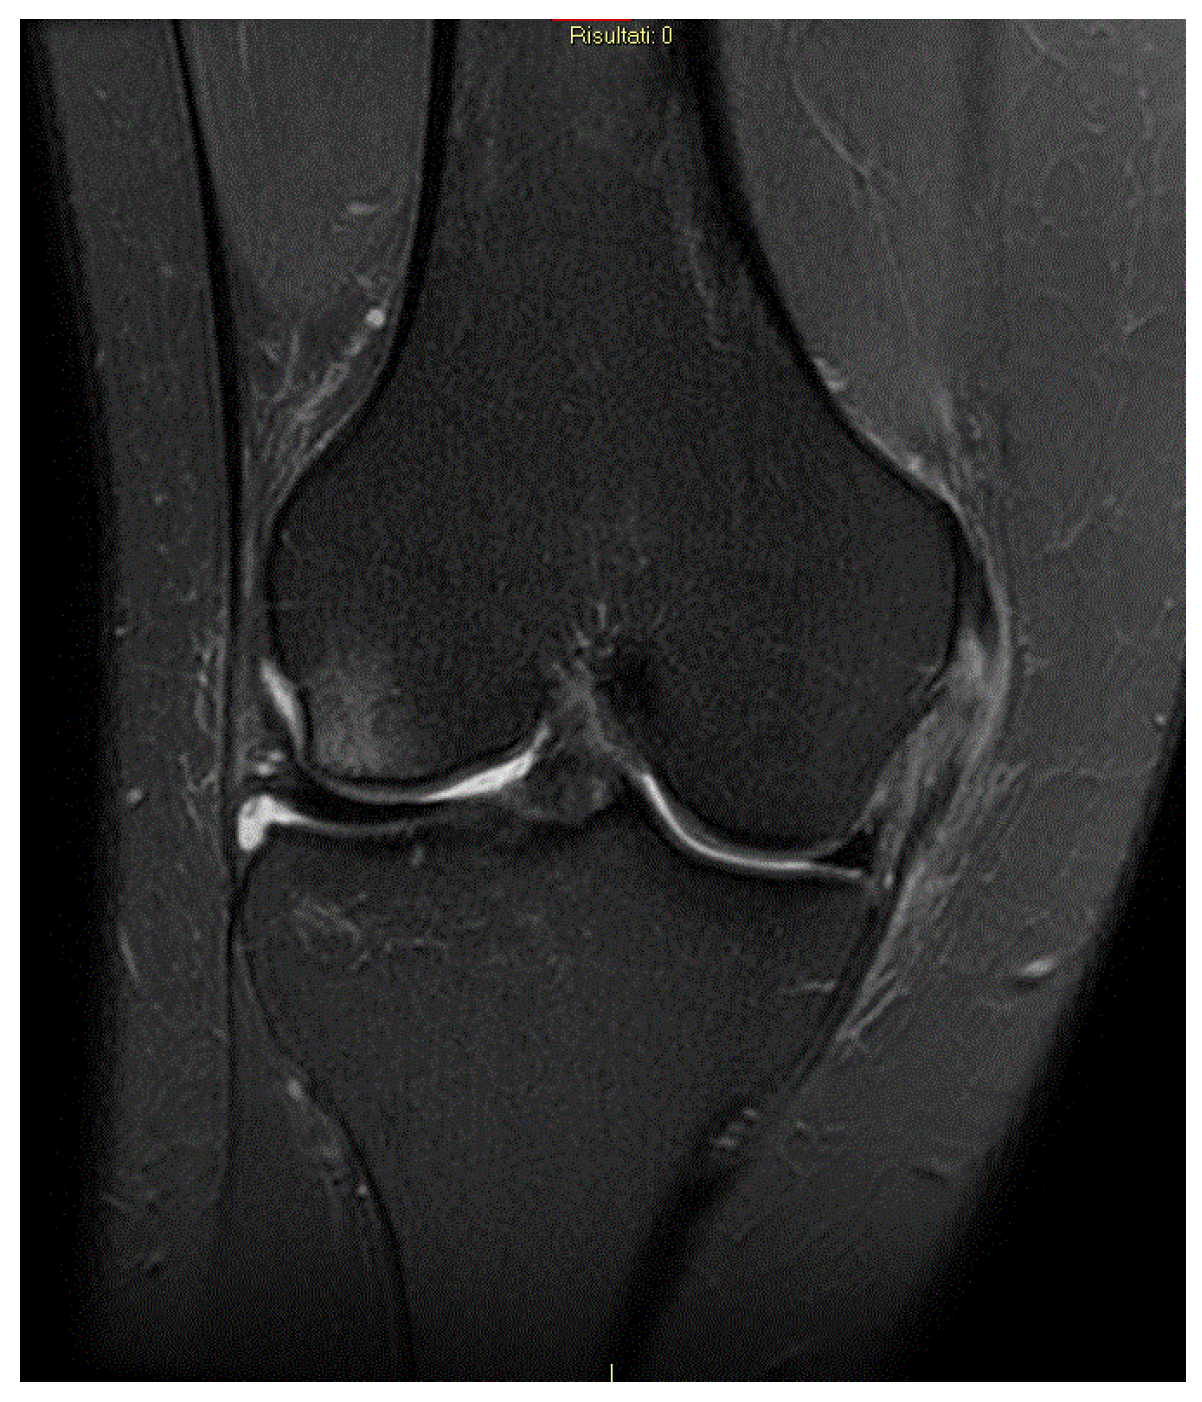

4.4. Magnetic Resonance Imaging (MRI) in the Diagnosis of ACL and MCL Injuries